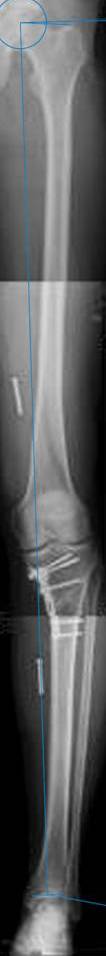

картинки оперированного пациента 40 лет, травма в 2006 году.

оперирован 06.11.2009г - корригирующая остеотомия большеберцовой кости.

Я картинку собрал с некоторыми погрешностями, если провести отвес от центра вращения головки бедра до середины голени (на пациенте),то имеется небольшой вальгус (гиперкоррекция)конечно она (гиперкоррекция) не достигает 10 гр, но 5 гр она достигает.

Проблема как сделать рентгеновские снимки а потом их совместить правильно, кто знает как решить этот вопрос. Ведь стандартные размеры рентгенкассет, оснащенные наши стационары отснять всю конечность с трех попыток!

Уважаемый д-р Батал Шушания,

К сожалению, не очень удачный пример. Если верить Р-граммам, имеет место быть дисплазия мыщелков бедренной кости с наклоном суставной линии. Это уже создает сложности получения хороших отдаленных результатов. Кроме того, по классике, необходима гиперкоррекция с созданием вальгуса 7-10 градусов для максимальной разгрузки медиального отдела КС. Если верить укладке, то линия сустава имеет четкий варусный наклон, поэтому результат операции м.б. кратковременным. В этих случаях показана двойная остеотомия бедра и тибии.

Если сделать правильно, то видно, что бедренная кость в порядке, а цель остеотомии (низкой, кстати), не достигнута вовсе.

Сохраняется варус. Для того, чтобы создать вальгусную гиперкоррекцию, не моделируя при этом откровенный Х голени, можно сделать медиализирующую остеотомию.